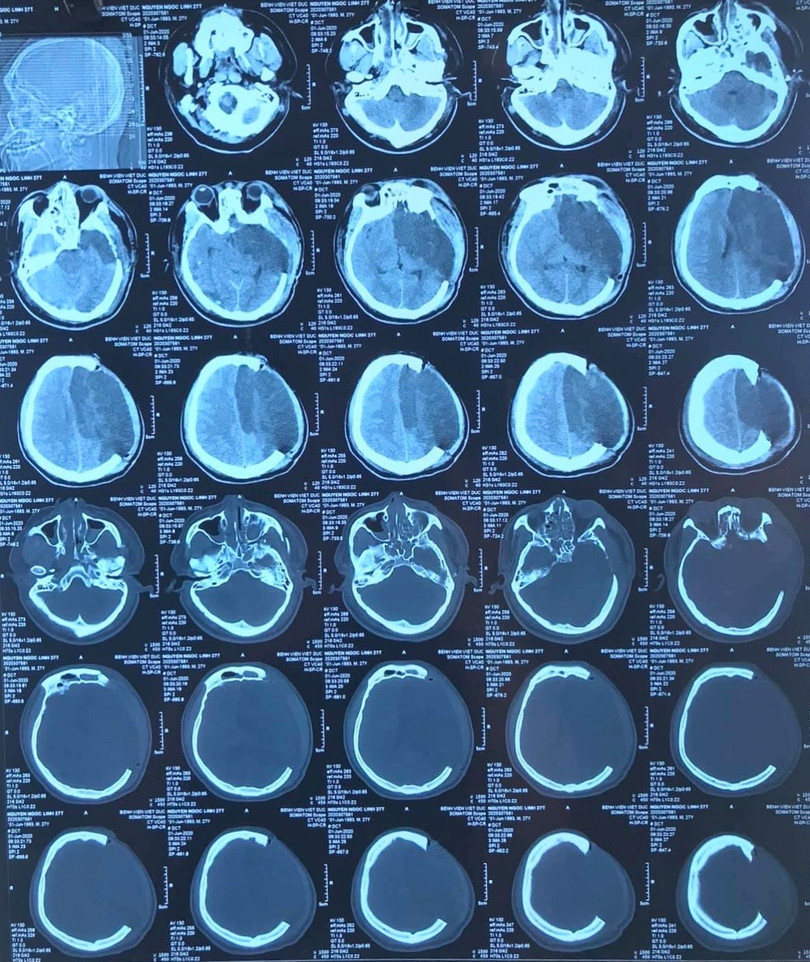

Anh N.N.L., 27 tuổi, sống ở Kiến Xương, Thái Bình không may bị ngã từ giàn giáo ở độ cao 7 m được chuyển đến Bệnh viện Hữu nghị Việt Đức vào ngày 3/6 trong tình trạng hôn mê sâu, hết sức nguy kịch.

Các bác sĩ chẩn đoán bệnh nhân bị chấn thương sọ não nặng, máu tụ DMC bán cầu T, nhồi máu bán cầu trái do hẹp động mạch cảnh trong trái, chấn thương ngực, đụng dập phổi hai bên, tràn khí trung thất. Chấn thương cột sống cổ: gãy gai sau C5C6.

| Ảnh chụp hộp sọ của bệnh nhân (Ảnh: BVCC) |